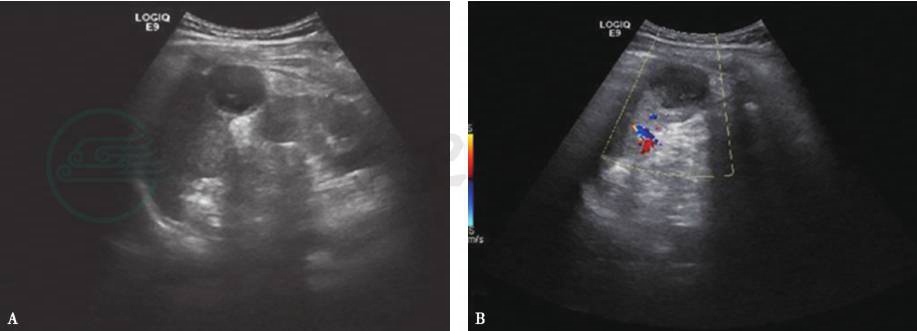

3.彩色多普勒显示其内无血流信号(图1)。行超声造影检查时,在静脉期可以显示脓肿的边缘和其内分隔。

图1脾脓肿彩色多普勒显示其内无血流信号

A.脾脓肿二维超声呈椭圆形低回声区,后方回声增强;B.彩色多普勒显示其内无血流信号